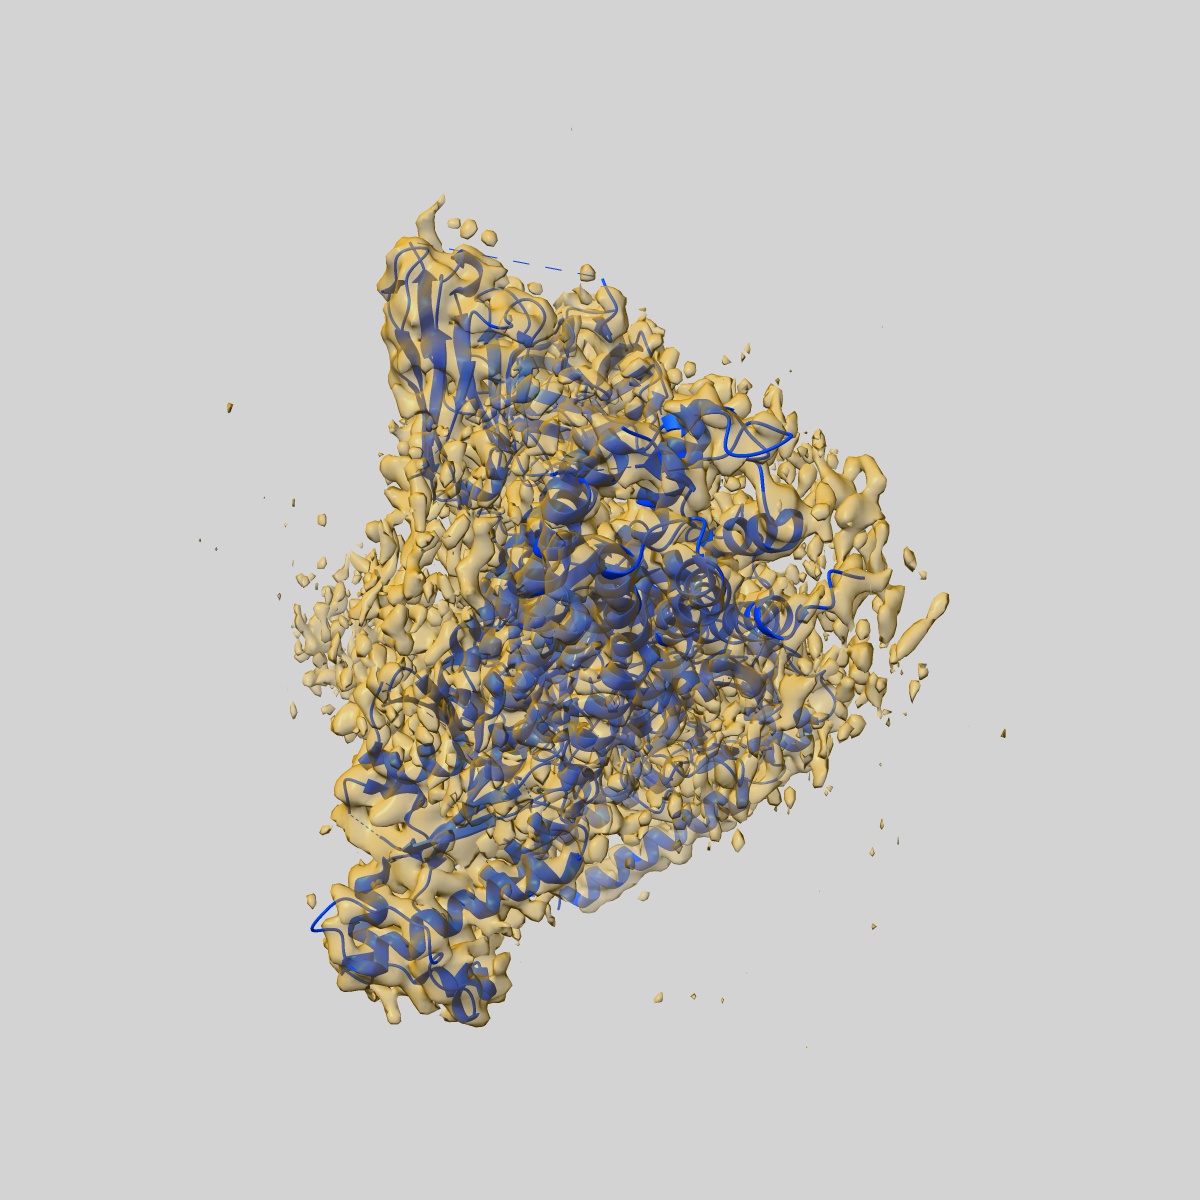

Structure of EP54-C3aR-Gq complex

Fitted models: 8i9a

Molecular basis of anaphylatoxin binding, activation, and signaling bias at complement receptors.